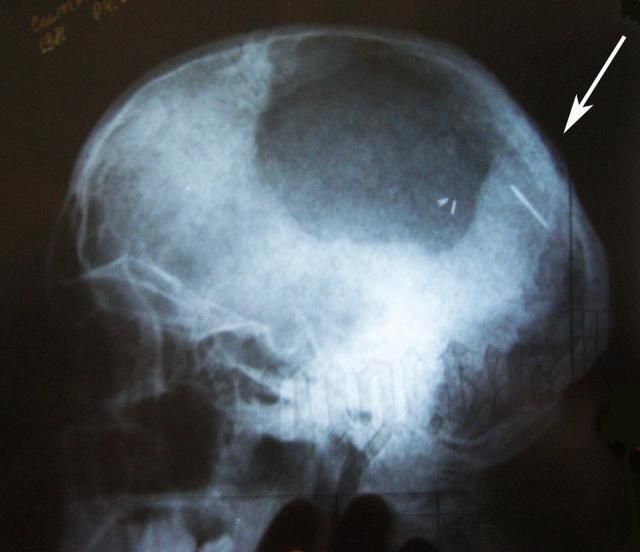

Жінка дізналася про голку в головному мозку після обстеження. Напередодні китаянка просто знепритомніла на роботі, тому й звернулася до медиків. Уже вони розказали про знахідку в голові пацієнтки.